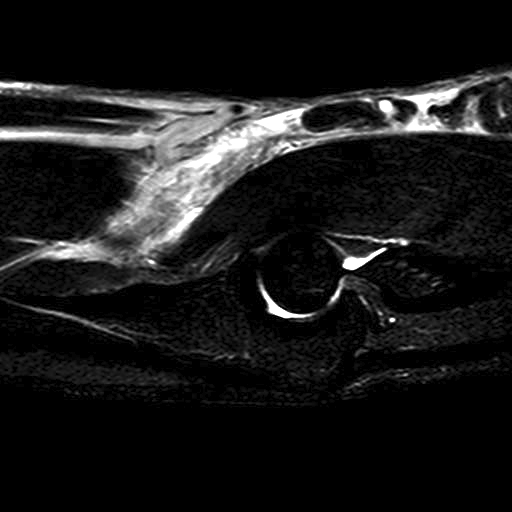

B.  Partial tear

Best evaluated on the axial view

- absence of low signal intensity biceps tendon insertion onto tuberosity

- present of soft tissue edema

MRI Biceps Partial TearBiceps Partial tear